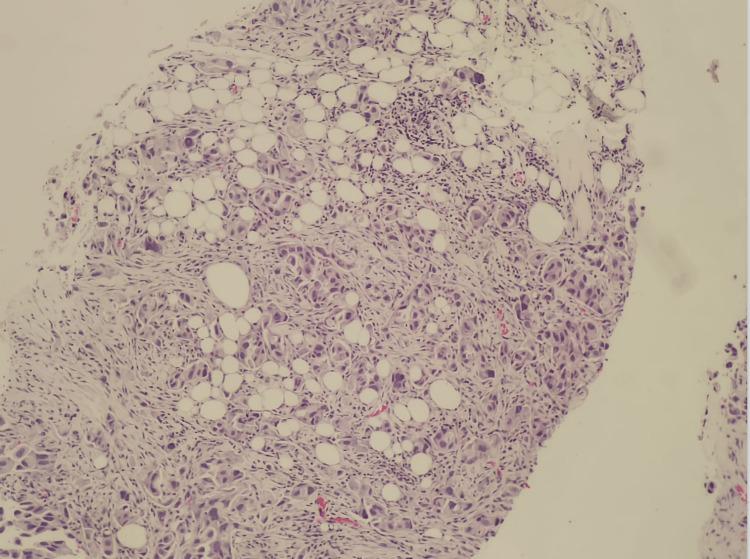

我们报告了沙特阿拉伯首例通过逆转录-聚合酶链反应技术证实存在 Kirsten 大鼠肉瘤病毒癌基因同源物(KRAS)G12C 突变的两例肺腺癌患者的病例系列。两名患者均为男性,年龄分别为 64 岁和 76 岁。第一名患者有重度吸烟史,而第二名患者未报告任何吸烟史。两例患者的肿瘤亚型均被确定为非黏液性肺腺癌。较年轻的患者表现为全身淋巴结肿大和右侧肺部肿块病变,而较年长的患者表现为 III - A 期左肺腺癌,需要快速治疗。对第一例病例的初步检查显示右侧纵隔移位、双侧颈部淋巴结肿大,以及右锁骨上核心活检的低分化肿瘤,导致采用姑息治疗并定期检查。第二例病例在确认生命体征稳定且实验室检查(中性粒细胞 100)后无发热症状。需要进一步开展研究,特别是针对大量来自阿拉伯湾地区的患者,以确认本国人群与国际人群之间的显著差异。此外,未来的研究应调查阿拉伯湾地区患者与其他患者之间 KRAS 突变型肺腺癌分化方面的更多差异。